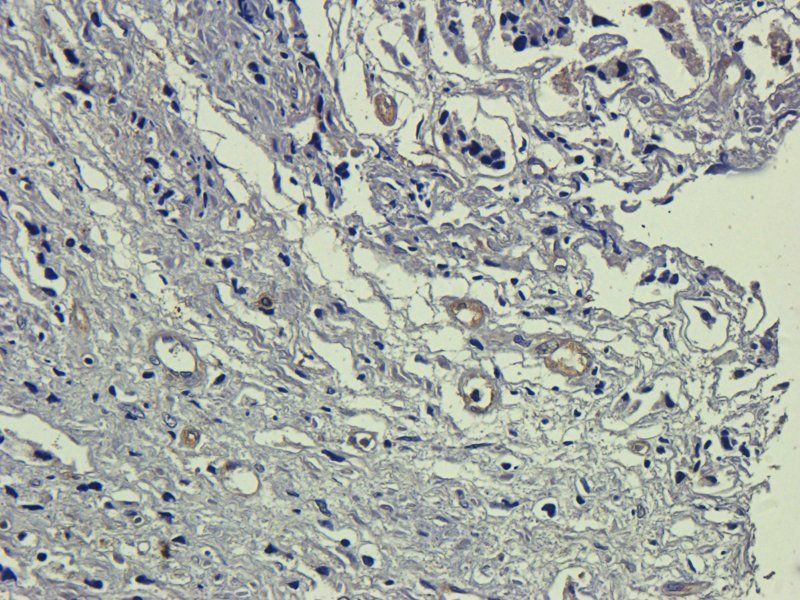

100 μg, 10 μg - Anti-Glucose Transporter GLUT1/SLC2A1 Antibody [orb259612]

FC, ICC, IF, IHC, IHC-Fr, WB

Human, Mouse, Rat

Rabbit

Polyclonal

Unconjugated